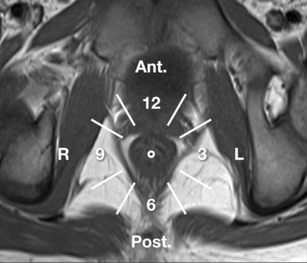

Perianal disease in pediatric Crohn disease: a review of MRI findings

Perianal complications of Crohn disease are a common occurrence in children and can result in significant morbidity when not accurately characterized prior to surgical intervention. MRI is an excellent imaging modality for the evaluation of perianal inflammatory bowel disease – allowing characterization and detailed description of perianal fistulas. MRI has many advantages over other imaging modalities for the pediatric patient. Radiologists will benefit from a sophisticated understanding of perianal anatomy, the classification of perianal fistulas, the advantages MRI offers in characterization of perianal fistulas as well as the common and incidental findings that are important in the MRI evaluation of perianal inflammatory bowel disease in children. Perianal fistulas are found at a high rate in pediatric referrals and are more commonly found in male patients.